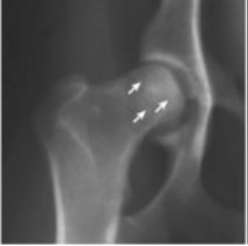

Name the abnormality marked with the arrows in the figure below. Be specific.

Grade 2 circumferential femoral head osteophyte (CFHO) is seen as a white line at the articular margin of the femoral head.